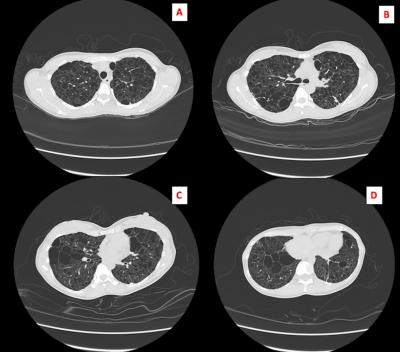

Figure 1: HRCT Thorax (A-D) showed bilateral diffuse cytic lesions of varying sizes